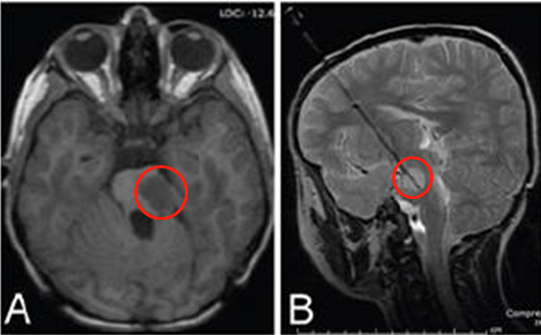

这名4岁男孩因头痛呕吐就医,检查结果显示其患有后颅窝髓母细胞瘤,随即接受了切除手术,并辅以化学疗法和干细胞治疗,但在他的二个化疗周期后,桥脑左侧见到复发性肿瘤(图A),这让他的父母焦虑。

即使患儿父母能够理解“手术切除”是较合适的解决办法,但他们实在不愿让孩子在短时间内接受两次开颅手术,因此在与医生进行了深入的沟通后,孩子接受了激光间质热疗(LITT)(图B),这是一种经皮微创技术,侵入性更小,但“威力”十足,是在一些脑部疾病的治疗方面更展现出了可媲美开颅手术的良好效果。